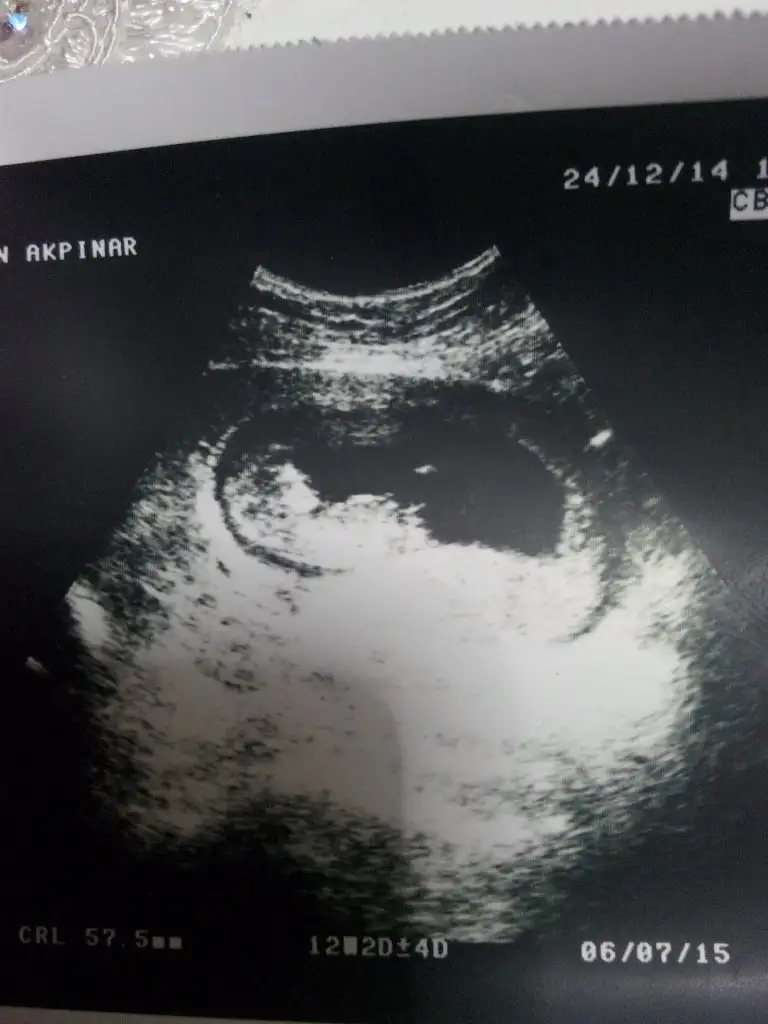

Ikı nub nasil anlamadım bu zaten 12 haftalıktı şuan 13 oldum ıkı kızım var bunu cok merak edıyorum yarın doktora gıdıcem bakalım ne olucakTerke erkek diyorum sanacanm ben pelo senin bebiste iki nubta görünüyor göbek kordonu ile karistrmiyorsam ppi görüyorum ama o krdonsa kiz olabilir 12haftalik fotosu varsa onu koy

teşekkürler canım sağolTerke erkek diyorum sanacanm ben pelo senin bebiste iki nubta görünüyor göbek kordonu ile karistrmiyorsam ppi görüyorum ama o krdonsa kiz olabilir 12haftalik fotosu varsa onu koy

Ataşehir sende çok kararsiz kaldim canm sen 13diyosun ama 12yaziyo ultrason goruntunde paralel nub var yani kiz gibi ancak kabarik duruyor erkeğe dönme olasiligida var oyuzden ne desem bilemedim